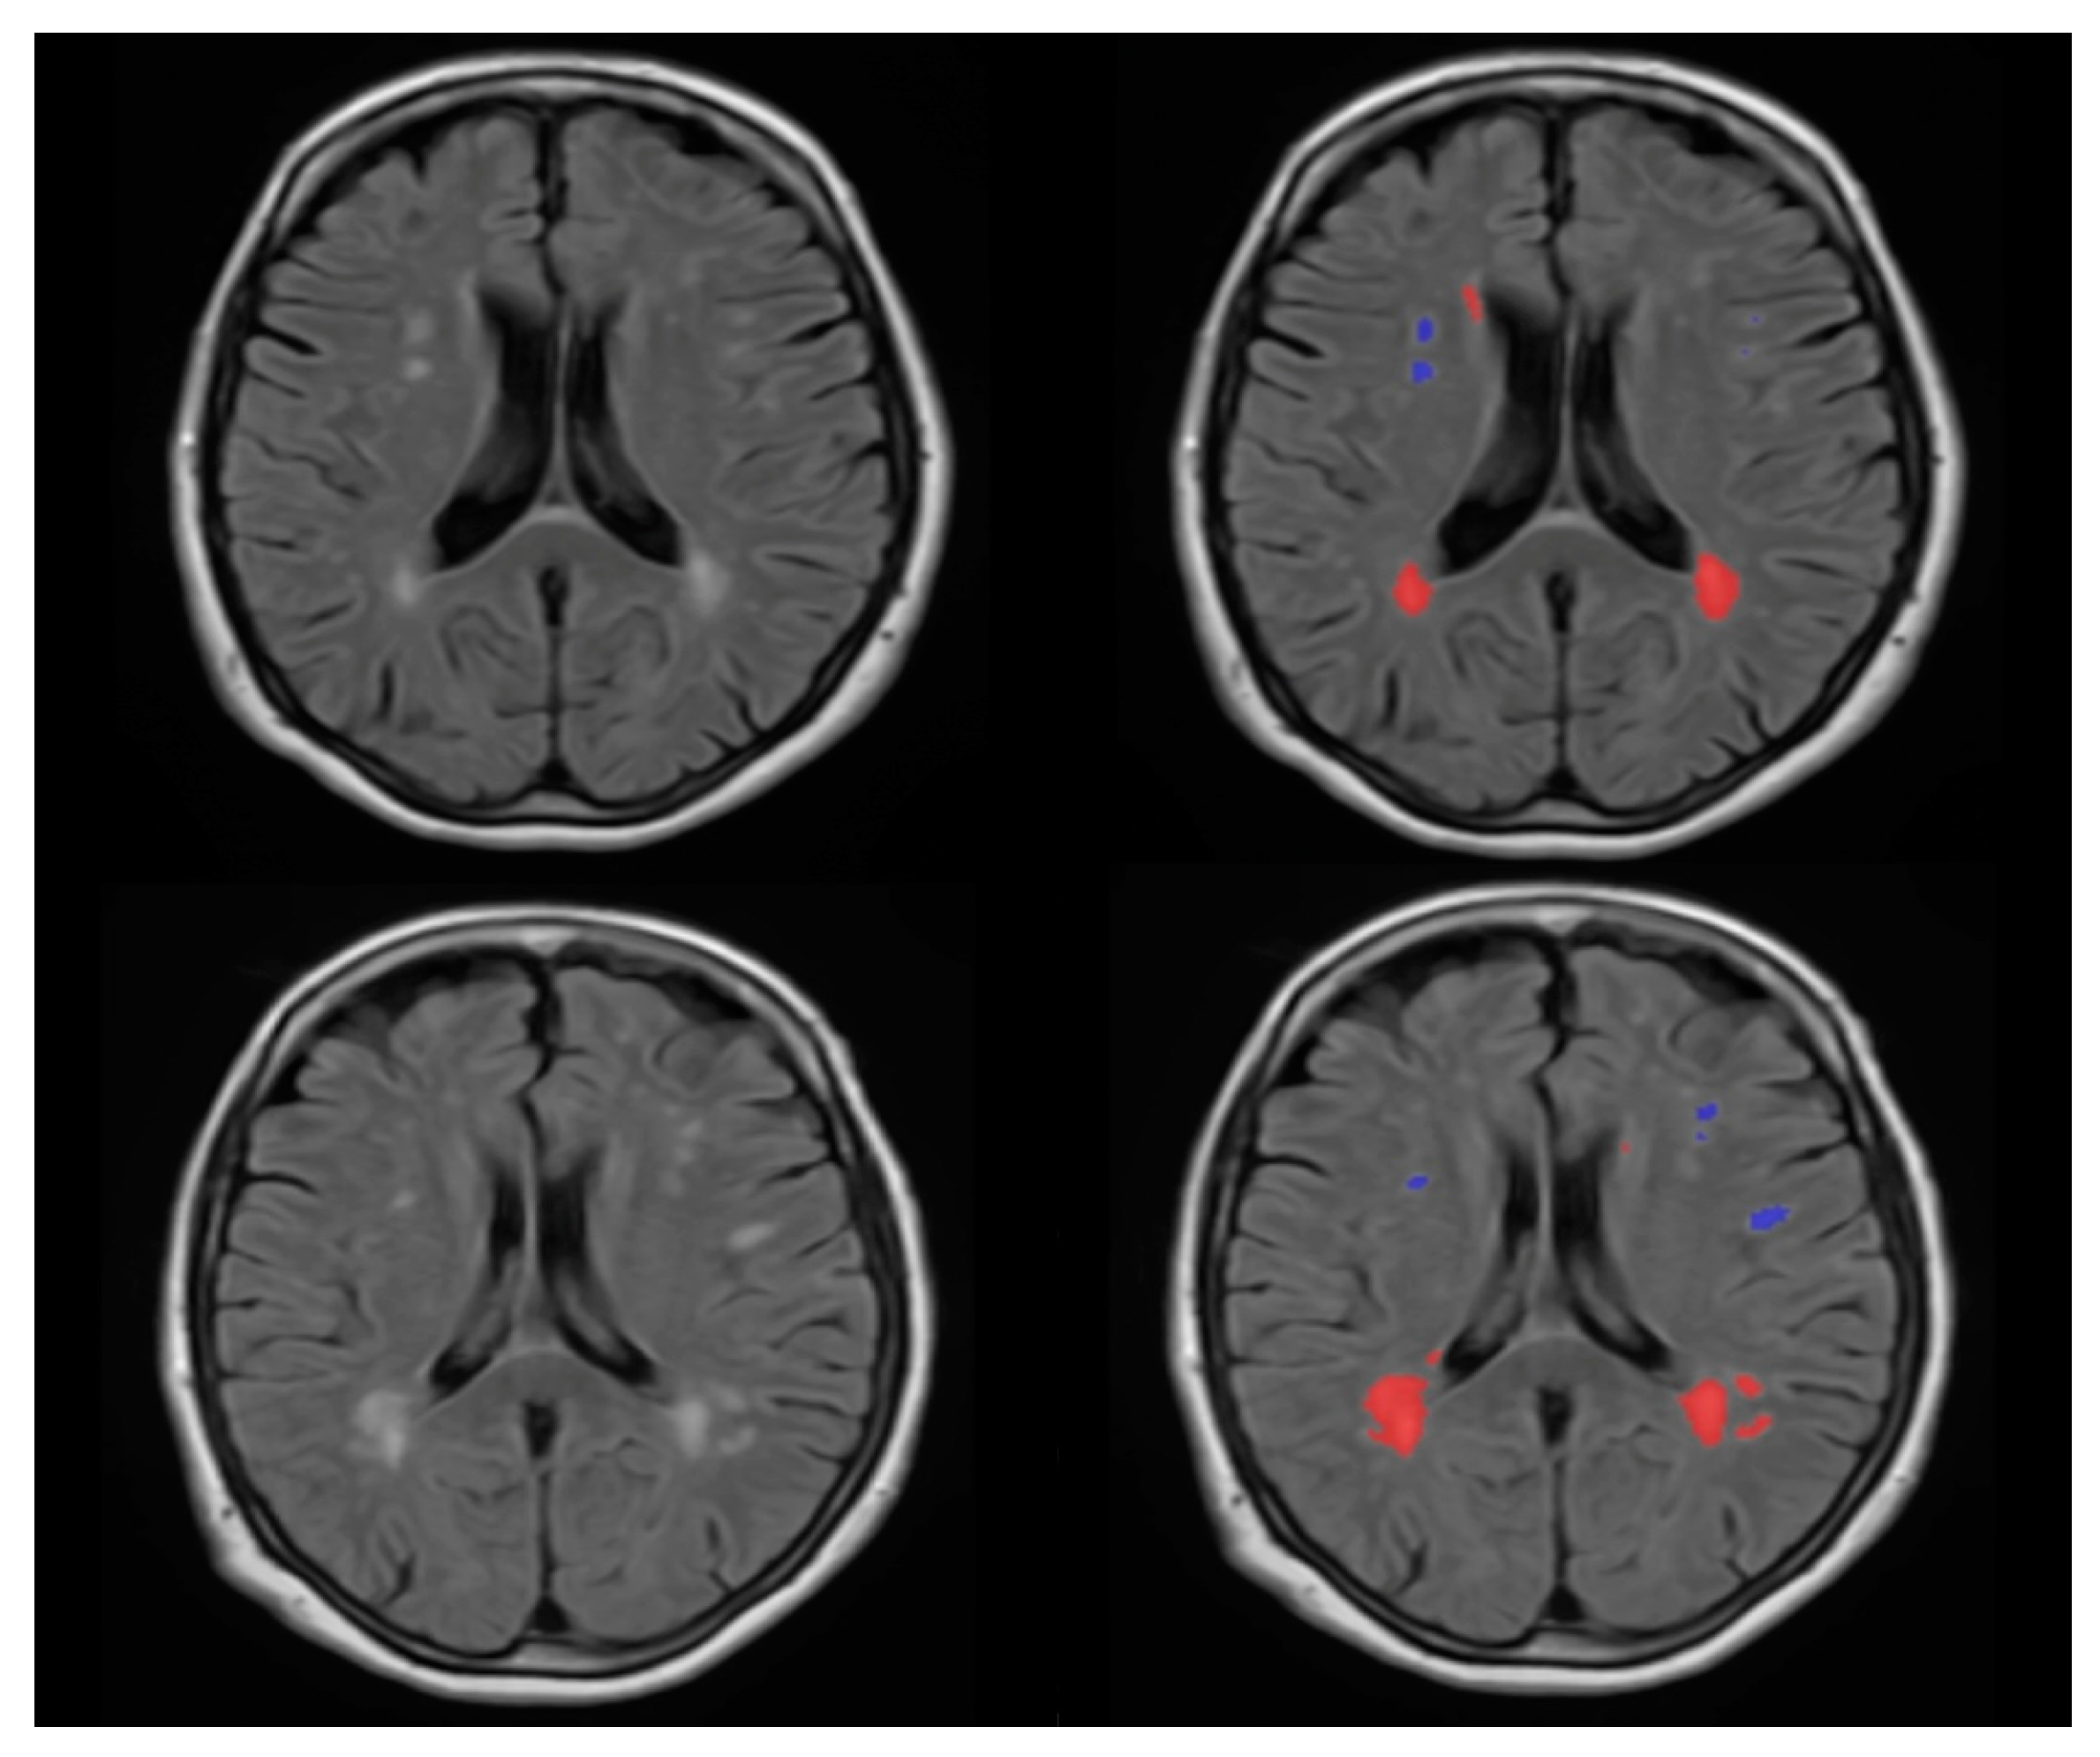

2.4. WMH Segmentation